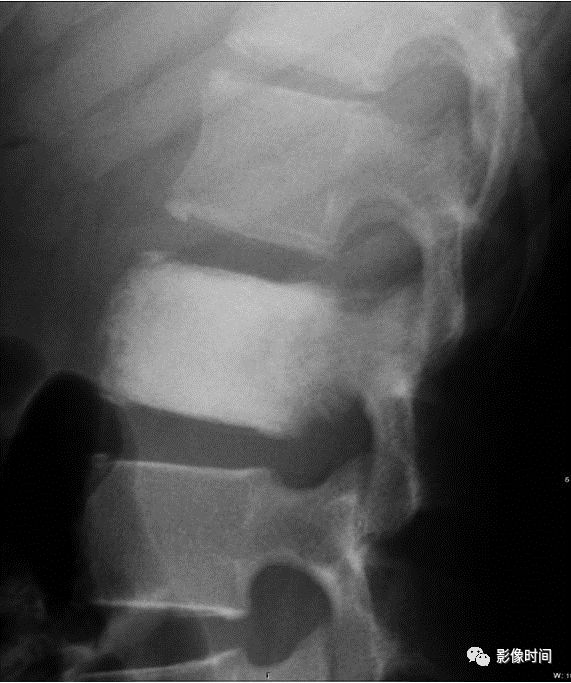

鱼椎(Fish vertebra),又称鳕鱼椎(codfish vertebrae)

所谓鱼椎是指椎体上下终板双凹导致的椎体形态改变,与鱼类椎体(双凹)形态相似而得名。这种凹陷是平滑的,与 H 型椎体的凹陷边界相对截然的不同。本征象通常用于描述成骨不全的椎体改变,但也可以见于骨质疏松症、肾性骨病、骨质软化、高胱氨酸尿症等疾病。

病例 1,1 岁男孩,成骨不全。腰椎侧位片示椎体密度减低,多发椎体双凹畸形,呈「鱼椎」样。

病例 2,骨质疏松症。CT 矢状位骨窗示椎体密度减低,骨小梁稀疏,多发椎体「鱼椎」样双凹变形。